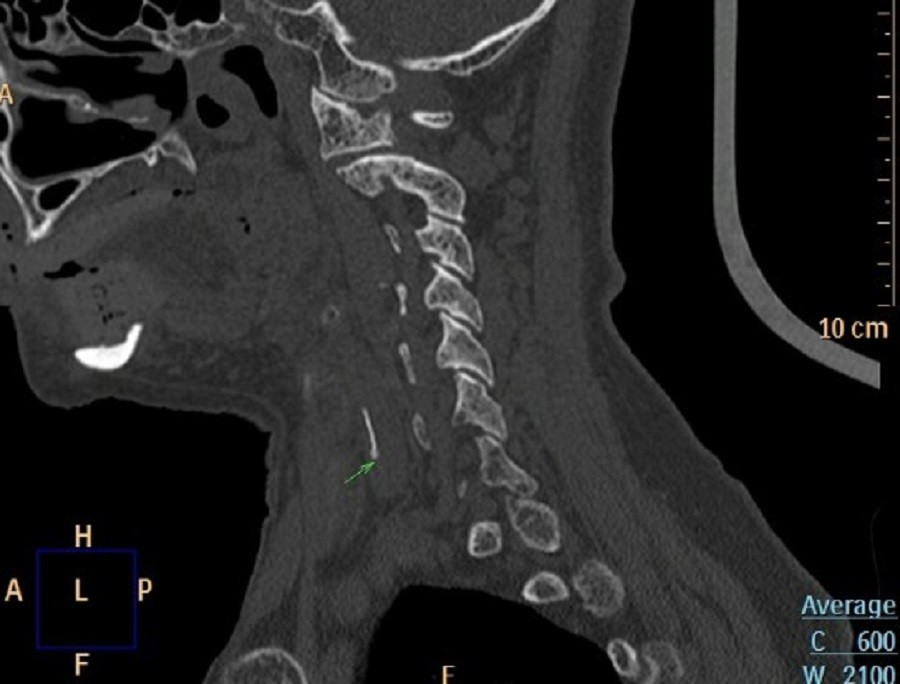

Chiếc xương cá (vị trí mũi tên) là thủ phạm khiến người bệnh phải nhập viện

Kết quả nội soi Tai Mũi Họng ghi nhận tình trạng phù nề nhiều ở vùng sụn phễu trái. Nội soi dạ dày – thực quản không phát hiện dị vật trong lòng ống tiêu hóa. Tuy nhiên, phim X-quang cổ nghiêng cho thấy hình ảnh nghi ngờ có dị vật. Để đánh giá chính xác, các bác sĩ chỉ định chụp CT và phát hiện một mảnh xương cá kích thước khoảng 1 x 22 mm đã xuyên ra khỏi đường tiêu hóa và cắm sâu vào thùy trái tuyến giáp.